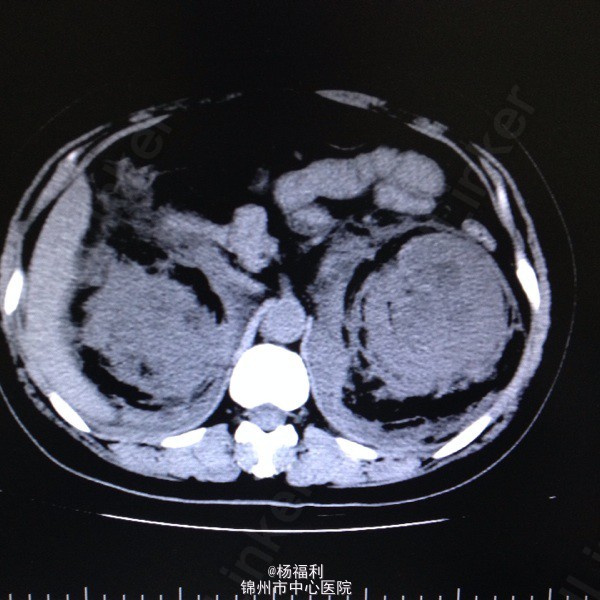

44岁女患。为消化科我会诊患者。 现病史:以上腹痛9小时为主诉入院。无发热及寒战、噁心未呕吐,无腹泻及黑便。 既往史:双眶炎性假瘤2年,口服激素治疗,并补钾。

查体:上腹部压痛,无反跳痛、右侧压痛明显,右肾区叩击痛,左肾区轻叩击痛,双输尿管走形区无压痛。 辅助检查;泌尿系彩超:双肾积水。 血白细胞:9.99*10^9。 肾功能正常。 全腹部ct及MRU检查:见图片。

诊断;真的不知道是啥病。 处理:暂时止痛处理。双肾病变。不知从哪里下手。